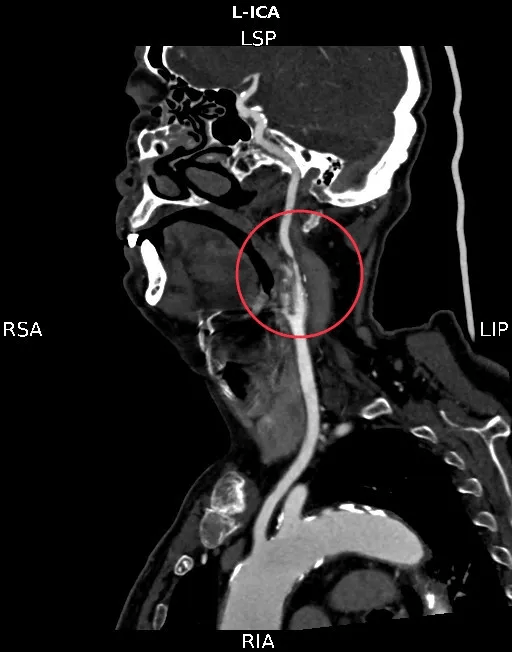

图片来源于网络,如有侵权,请联系删除